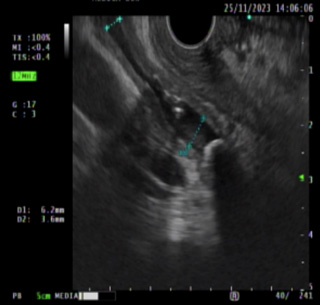

Imagen 4. Piedra en el conducto biliar. |